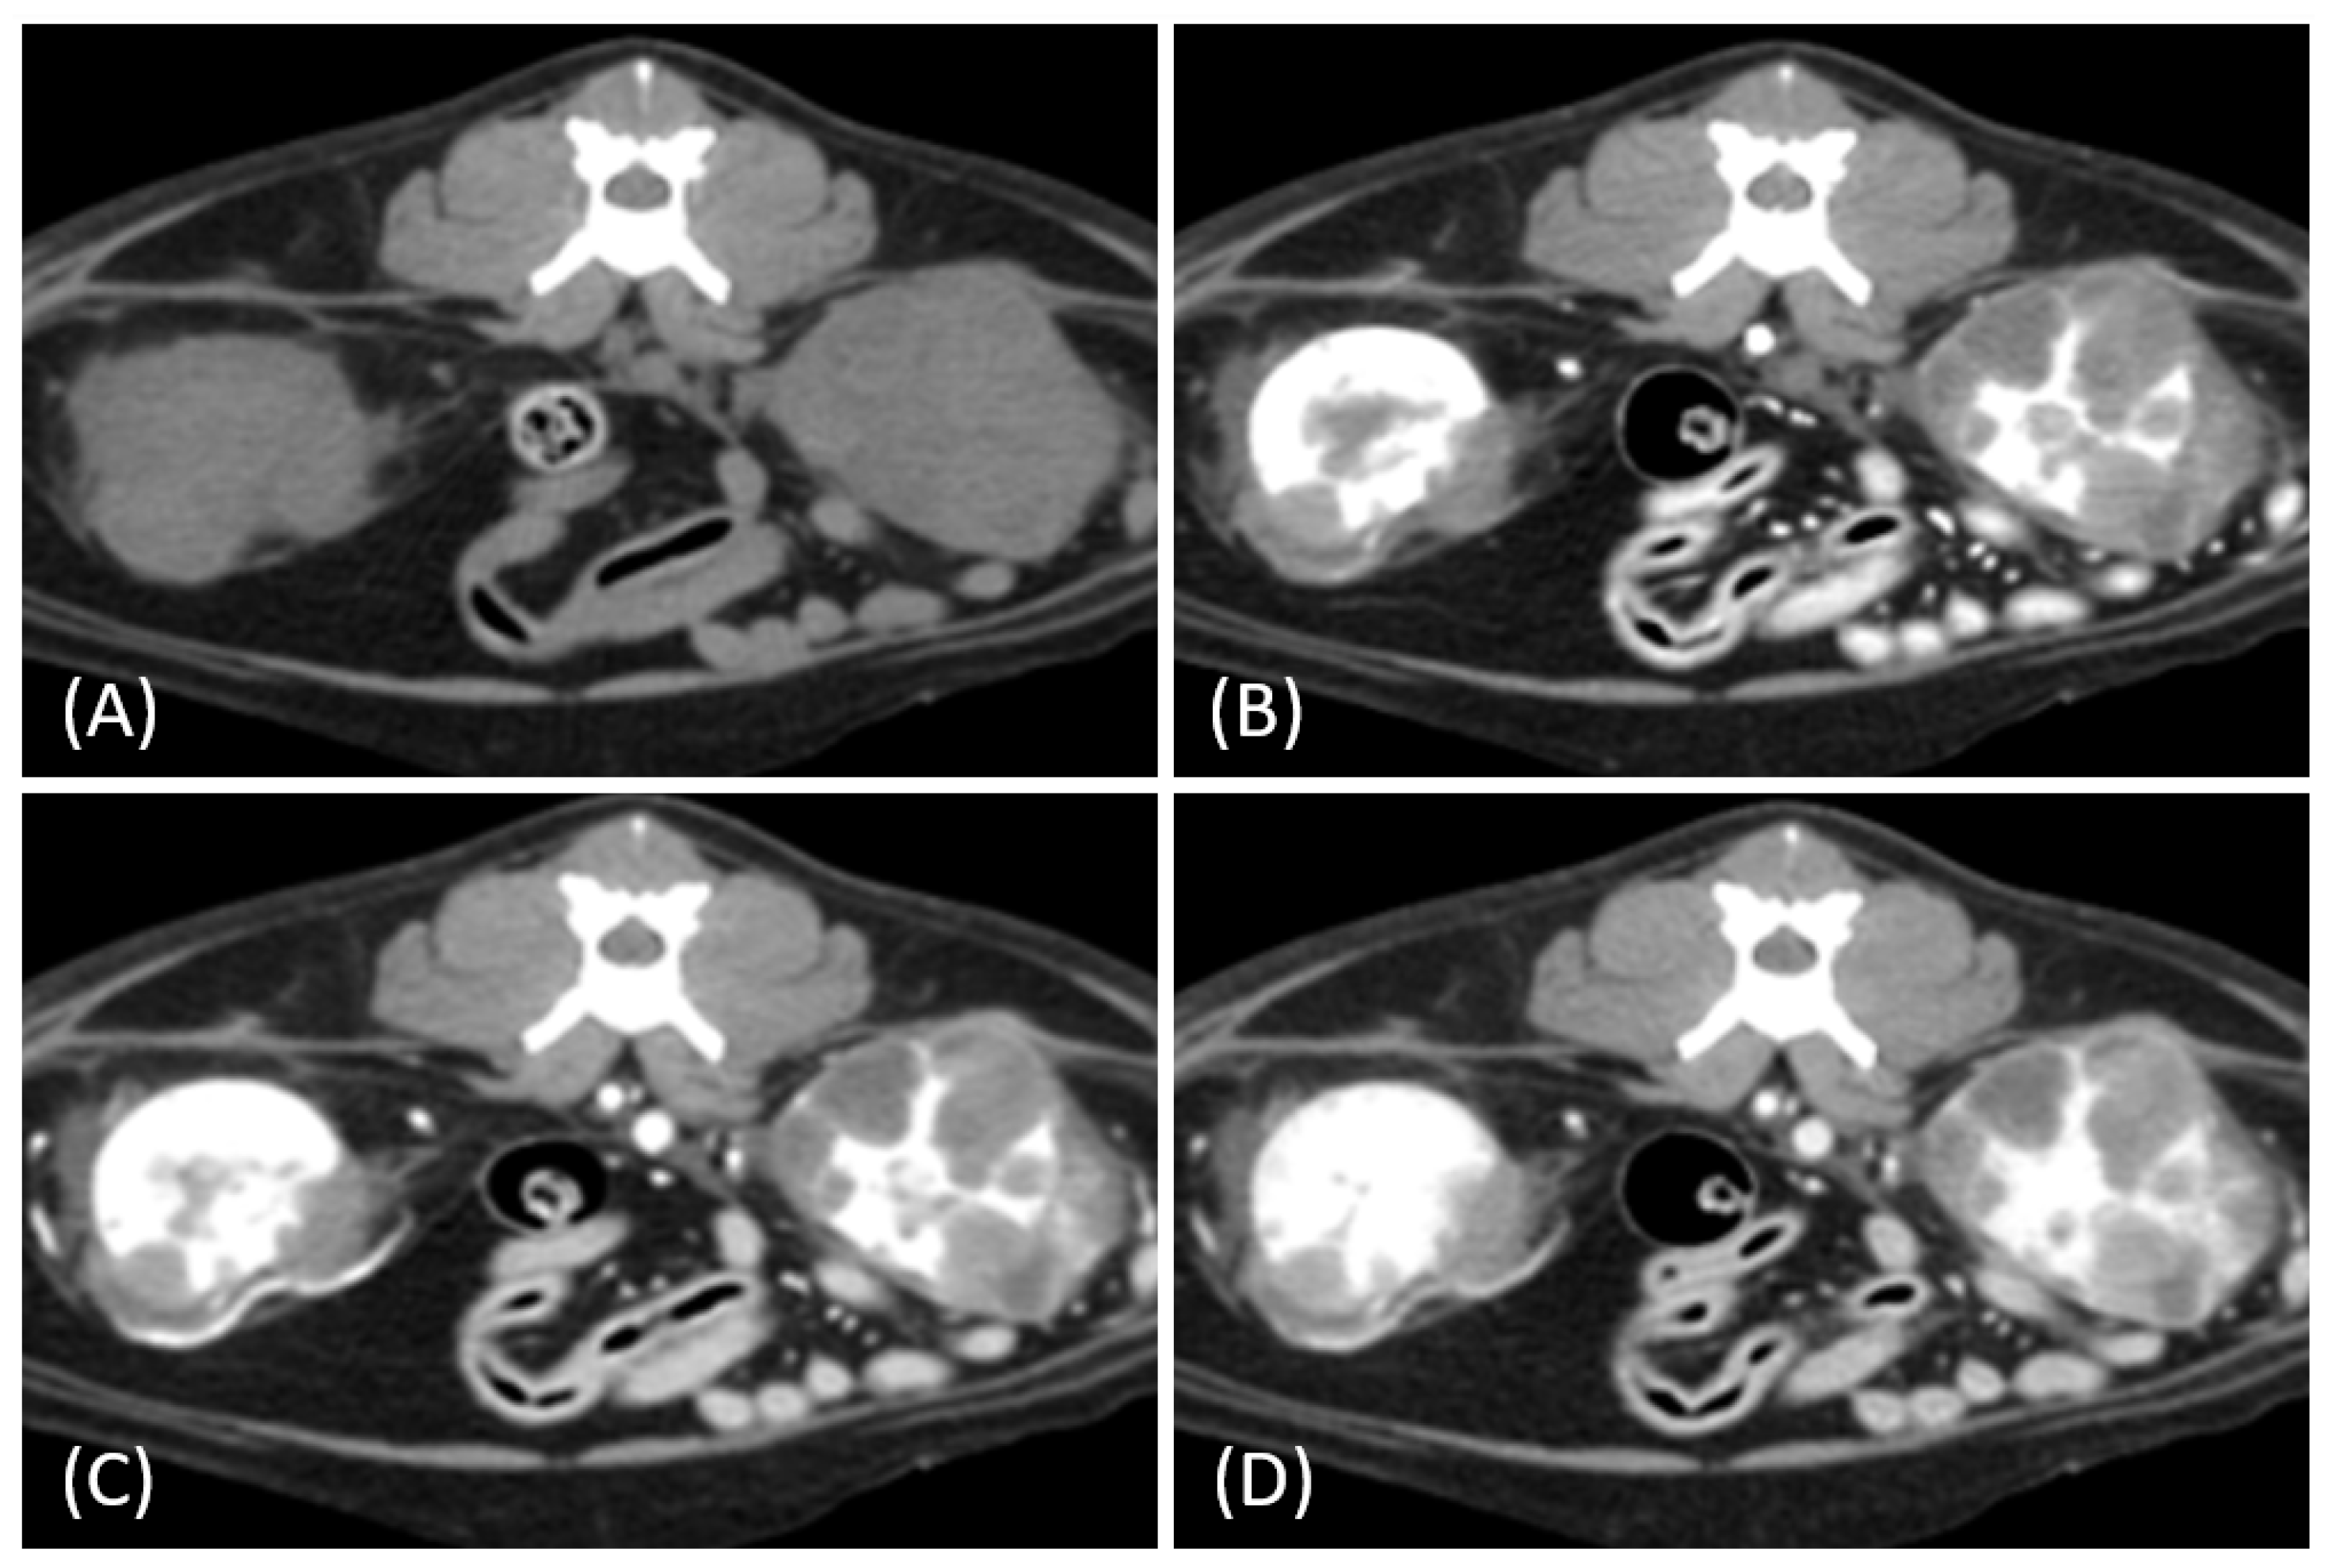

Figure 2.

(A) Pre-contrast, (B) corticomedullary phase, (C) nephrographic phase, and (D,E) late nephrographic/early excretory phase contrast-enhanced computed tomography (CT) images of a cat with a unilateral left renal cell carcinoma. The tumor demonstrates predominantly heterogeneous and plateau enhancement patterns throughout the phases, with focal areas of intense enhancement visible during the corticomedullary phase.

Tumor growth patterns differed significantly between RCC and lymphoma cases (p = 0.015). RCC predominantly exhibited an expansile growth pattern (11/15, 73.3%) (Figure 1 and Figure 2), while infiltrative patterns were observed in three cases (3/15, 20%) and a combined pattern in one case (1/15, 6.7%). In contrast, lymphomas showed more variable patterns, with infiltrative growth being the most common (5/10, 50%), followed by combined (3/10, 30%) and expansile patterns (2/10, 20%) (Figure 3).

The spatial enhancement pattern differed significantly between the two tumor types (p < 0.001), with RCC typically showing heterogeneous enhancement (13/13, 100%) and lymphomas displaying homogeneous enhancement (9/10, 90%). However, one lymphoma case demonstrated a heterogeneous enhancement pattern (Figure 6A). Tumor vessel enhancement in the corticomedullary phase was observed exclusively in the RCC cases (4/5, 80%) (Figure 1B), while none of the lymphoma cases showed this feature (0/6, 0%) (p = 0.015).

The time-course enhancement pattern analysis revealed different characteristics between the RCC and lymphoma cases. Among the RCC cases with available three-phase enhancement data (n = 5), three cases (3/5, 60%) showed a progressive enhancement pattern (Figure 1), while two cases (2/5, 40%) demonstrated a plateau pattern (Figure 2). By contrast, all the lymphoma cases with available data (n = 6) exhibited progressive enhancement patterns. However, the difference in the time-course enhancement patterns between the two tumor types was not statistically significant (p = 0.182).